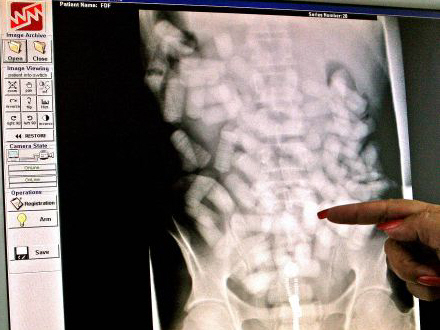

Det er tydeligt at se poserne med narko på scanningsbilleder

Skat kan ikke oplyse, hvordan de spotter smuglerne, fordi det kan give bagmændene gode idéer. Men tolderne sender alligevel en advarsel til smuglerne. Til foråret anskaffer Skat nemlig en kropscanner, der på stedet kan afsløre smuglere med stoffer under huden.

I dag sender toldere først mistænkte smuglere videre til politiet efter en afhøring. Politiet kører så den mistænkte til hospitalet, der scanner personen. I Billund Lufthavn har de som tidligere nævnt taget en enkelt smugler, der rejste fra Spanien, med et kilo kokain i år, men politiet er opmærksomme på, at en scanner i København kan starte en hel bølge af slugere til Billund.